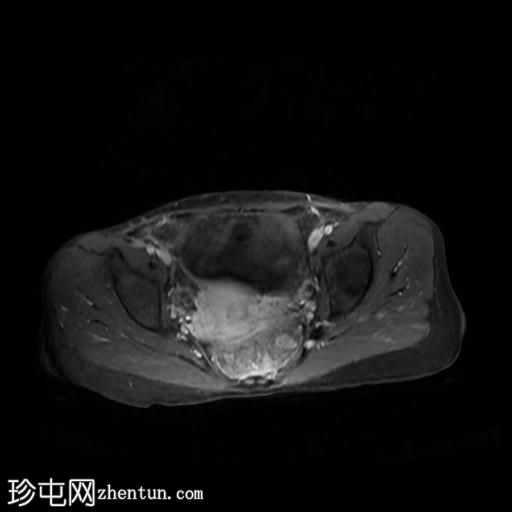

轴位

T2加权像

回肠末端及盆腔回肠肠袢可见长段肠壁增厚及强化,肠周血管丰富,呈“梳状征”,并可见明显的纤维脂肪浸润。

未见瘘管、积液、腹水或梗阻。

磁共振肠道造影(MRE)结果支持克罗恩病的诊断,显示远端及末端回肠以活动

性病

变为主,并可见明显的肠周血管。